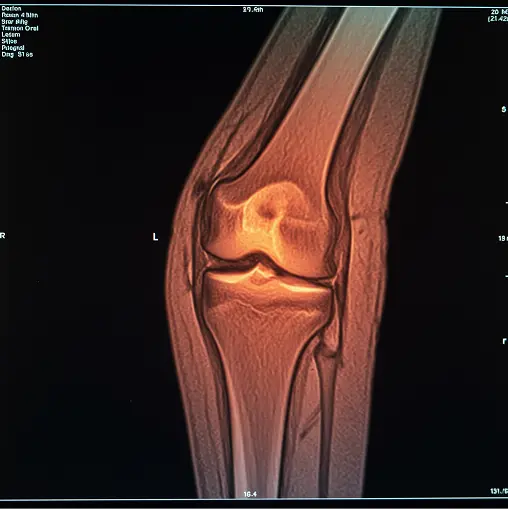

무릎 관절 MRI (Magnetic Resonance Imaging)는 강력한 자기장과 라디오파를 이용하여 무릎 내부의 뼈, 연골, 인대, 근육, 힘줄 등의 연부 조직을 고화질 단면 이미지로 만들어내는 진단 검사 방법입니다.

단순 X-ray로는 확인하기 어려운 미세한 연골 손상, 인대 파열, 물혹, 염증 등을 명확하게 진단할 수 있어, 통증의 정확한 원인 파악과 그에 맞는 적절한 치료 계획을 세우는 데 결정적인 역할을 합니다. 오래 지속되는 통증이나 심한 외상 후 상태를 확인할 때 특히 필요합니다.